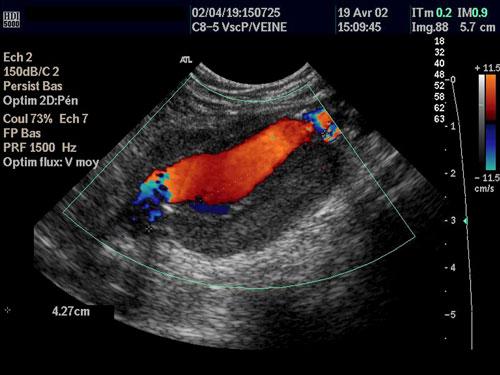

现今多数的医学治疗都会不同程度地对人体构成伤害,比如:外科手术虽然是病症治疗手段,但是手术刀对人体的创伤是不容忽视的。目前,一种超声波治疗措施将有效解决这一矛盾。

美国西雅图市华盛顿大学的劳伦斯·克鲁姆(lawrence crum)称,一种超高强度的超声波可以烧灼出血的动脉血管。他所在的超声波科技公司研制出一种手持式设备,可使外科医师对人体内部富含血液的器官进行切割手术,在切割之后立即对血管进行烧灼愈合,这样的手术方法无需在人体皮肤上切割伤口。目前,无创口手术治疗已在动物实验中取得了成功,预计今年将进入人体临床实验。